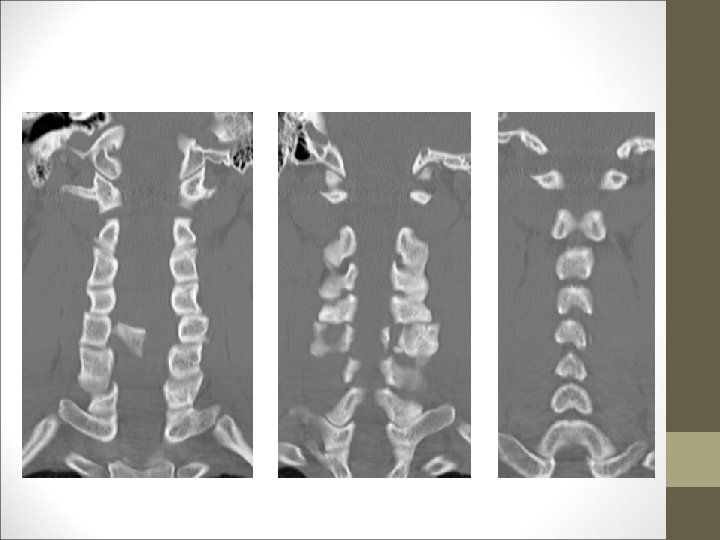

FACULTAD DE MEDICINA DEPARTAMENTO DE CIRUGÍA NEUROCIRUGÍA ¿Qué harías? TAC Cervical

TC Desplazamientos de fragmentos óseos ¿Algo mas? Desplazamientos discales y lesiones ligamentosa FACULTAD DE MEDICINA DEPARTAMENTO DE CIRUGÍA NEUROCIRUGÍA RM